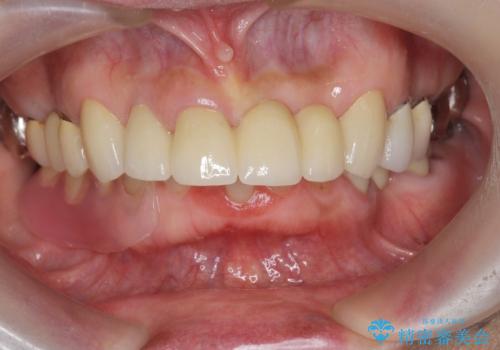

抜歯後の見た目改善として深い咬合関係であることからインプラントは避け、ブリッジで補綴治療を行っていくこととしました。

- 72.6万円(仮歯・ジルコニアクラウン×6)費用は治療当時の料金となります

元々の噛み合わせが深く(ディープバイト)、転んで顎を強打したことで上顎前歯2本が根元から折れてしまい抜歯をしなければいけない状況となってしまいました。

今後前歯への負担を減らすためにナイトガードマウスピースを使用していただき歯の保存に努めていきます。